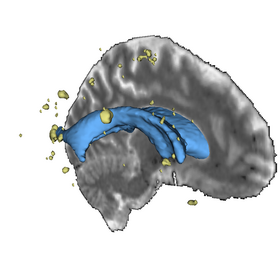

We obtained gray matter, white matter, CSF, and lesion maps for each subject based on T1-weighted, T2-weighted, and FLAIR images. Ultimately, the NA-MIC Kit will provide a workflow for individual and group analysis of lesions. It will be implemented as a set of Slicer3 modules that can be used interactively within the Slicer3 application as well as in batch on a computing cluster using BatchMake.

- Scully M, Anderson B, Lane T, Gasparovic C, Magnotta V, Sibbitt W, Roldan C, Kikinis R and Bockholt HJ (2010) An automated method for segmenting white matter lesions through multi-level morphometric feature classification with application to lupus. Front. Hum. Neurosci. 4:27. doi:10.3389/fnhum.2010.00027. Available here